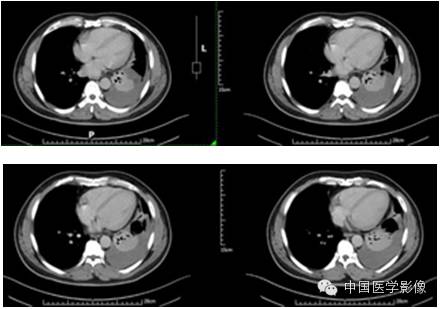

【影像资料】

动脉期

静脉期

延迟期

【病理结果】

孤立性纤维性肿瘤